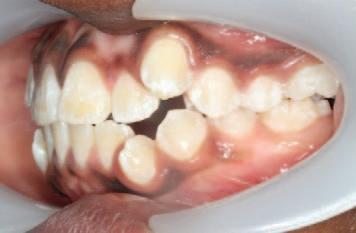

Oral leukoplakia may be subclassified into homogeneous and non-homogeneous forms. Homogenous oral leukoplakia (Figure 1) is characterised by a predominantly flat, uniform, often well-demarcated white patch, with a consistent surface topography, and it usually lacks symptoms.1 When homogenous oral leukoplakia is found on the floor of the mouth, it can have a distinctive ebbing tide appearance (Figure 2).

FIGURE 1: Homogenous oral leukoplakia on the lateral border of the tongue.